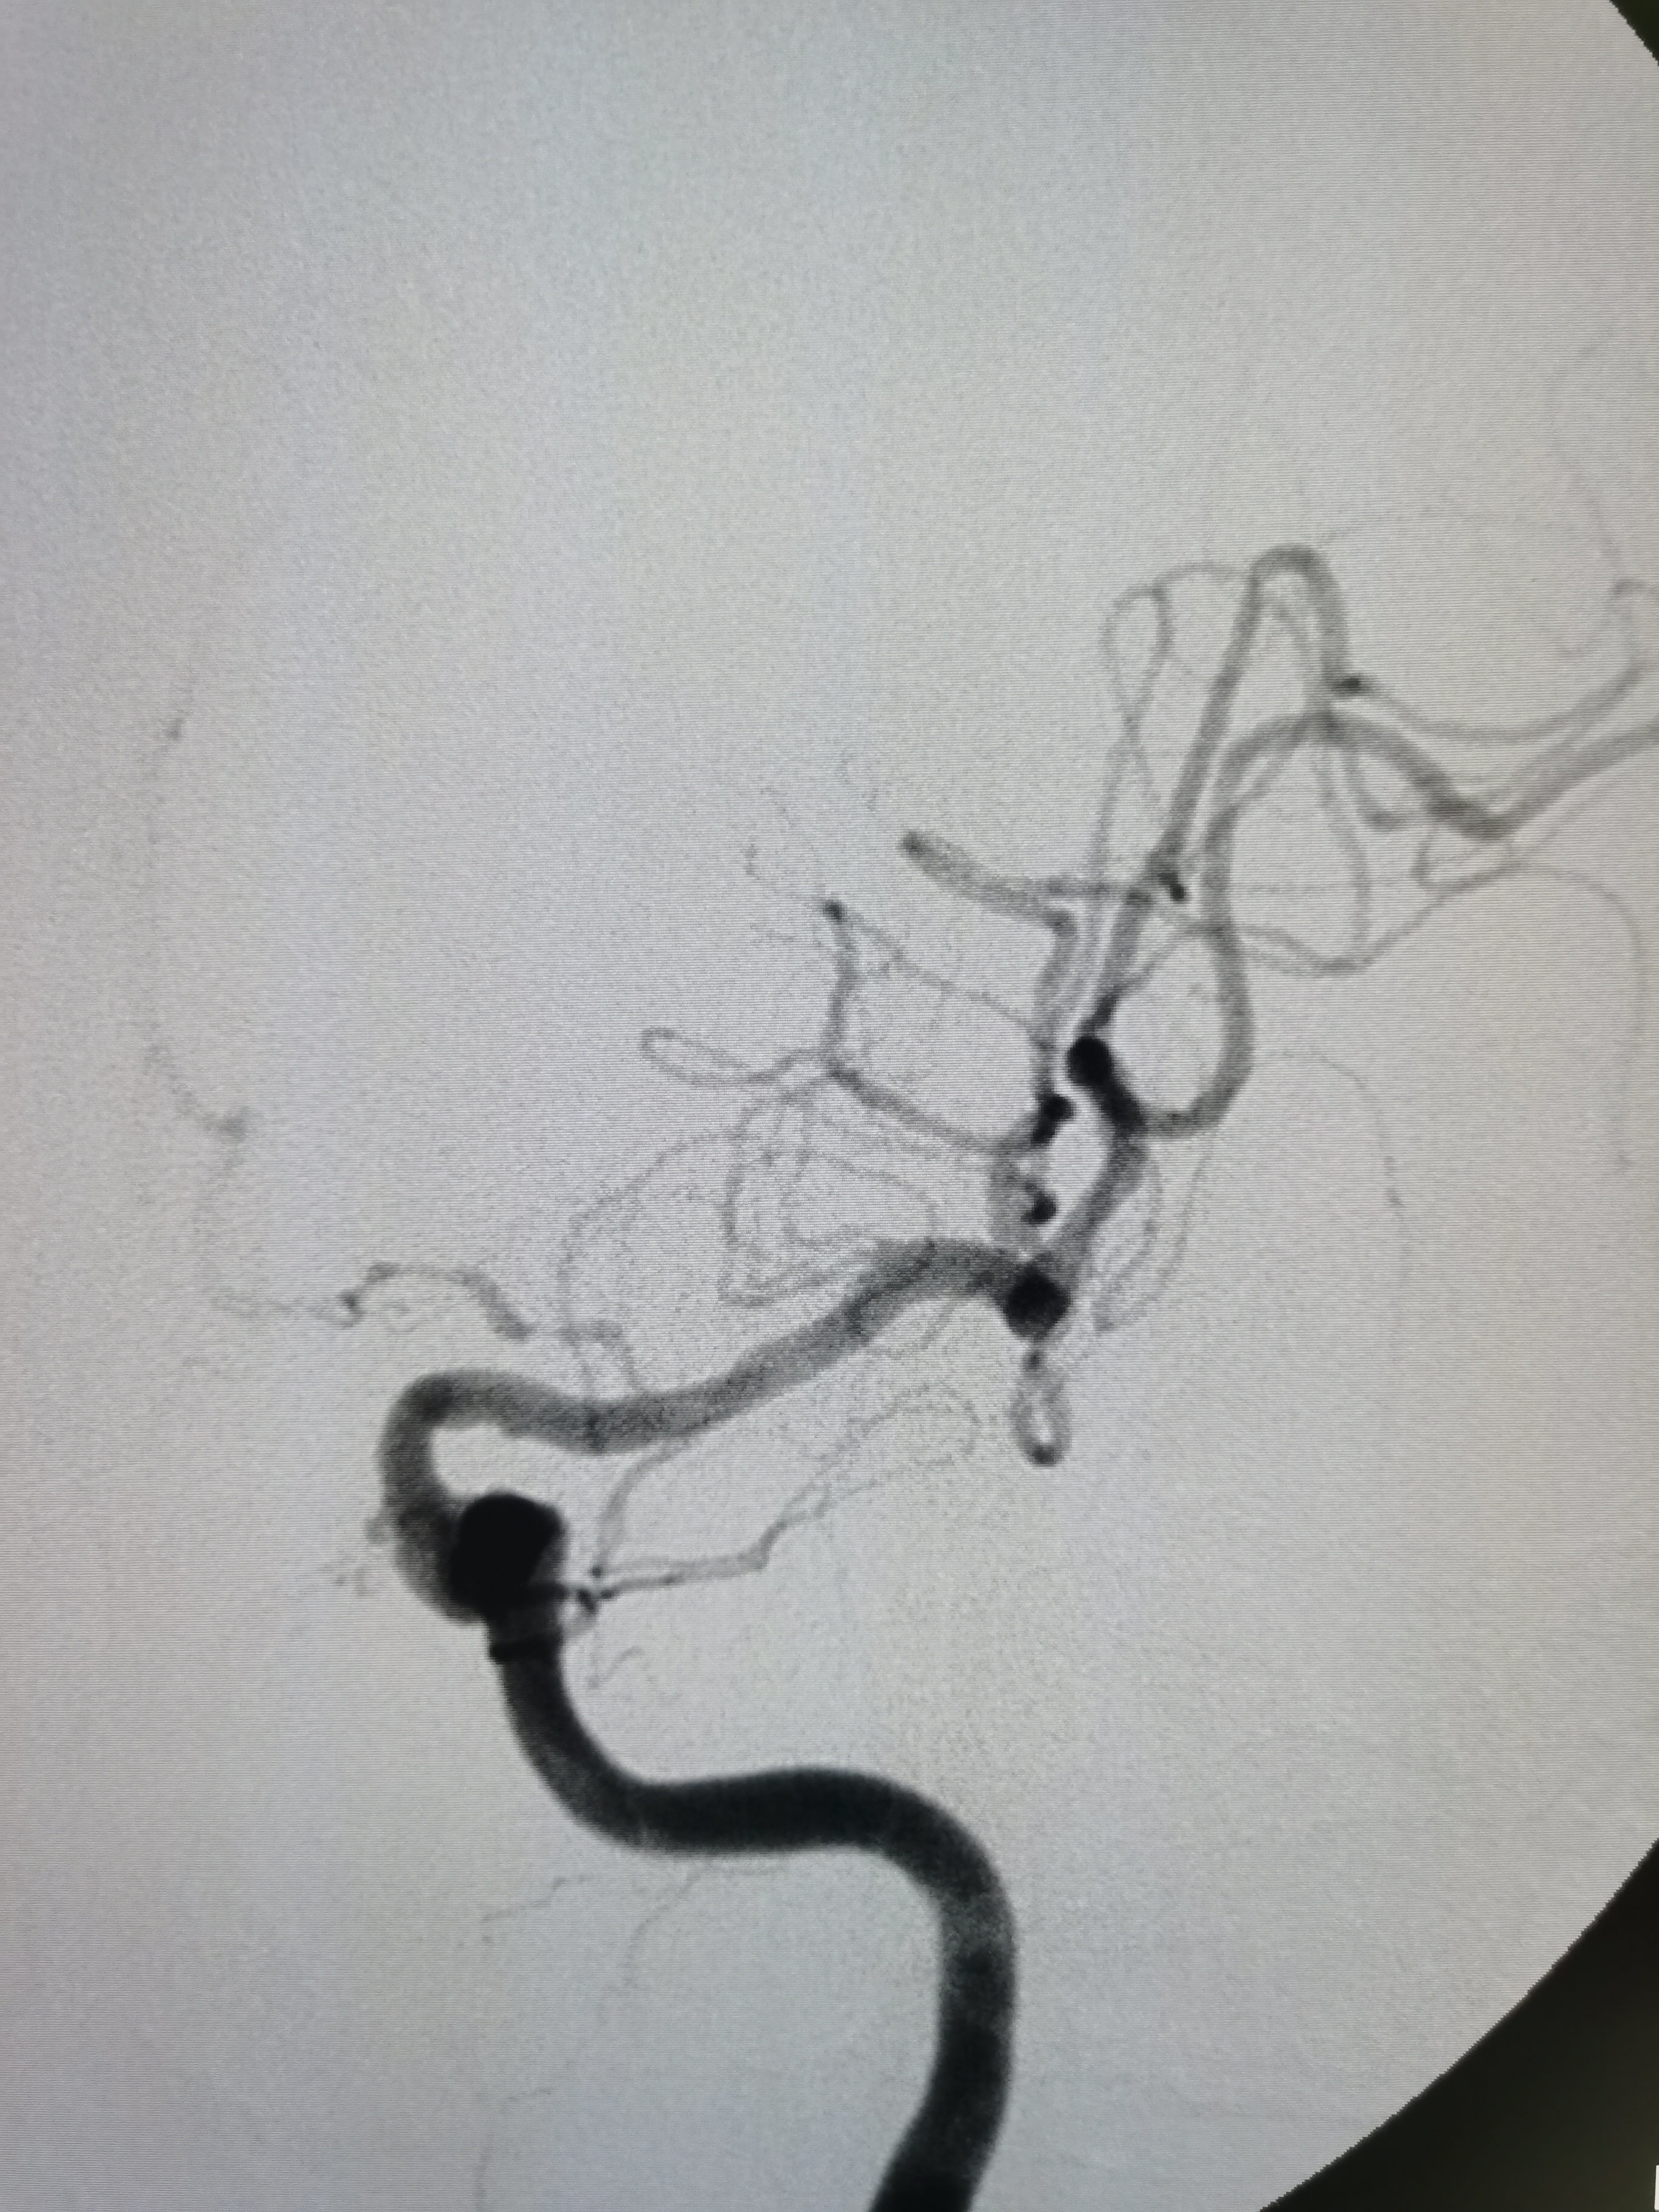

球扩后造影见狭窄解除,豆纹动脉显影良好,远端血供改善,未见夹层征象。

正位造影见狭窄解除,颅内血流通畅。

观察15分钟后造影未见明显弹性回缩。